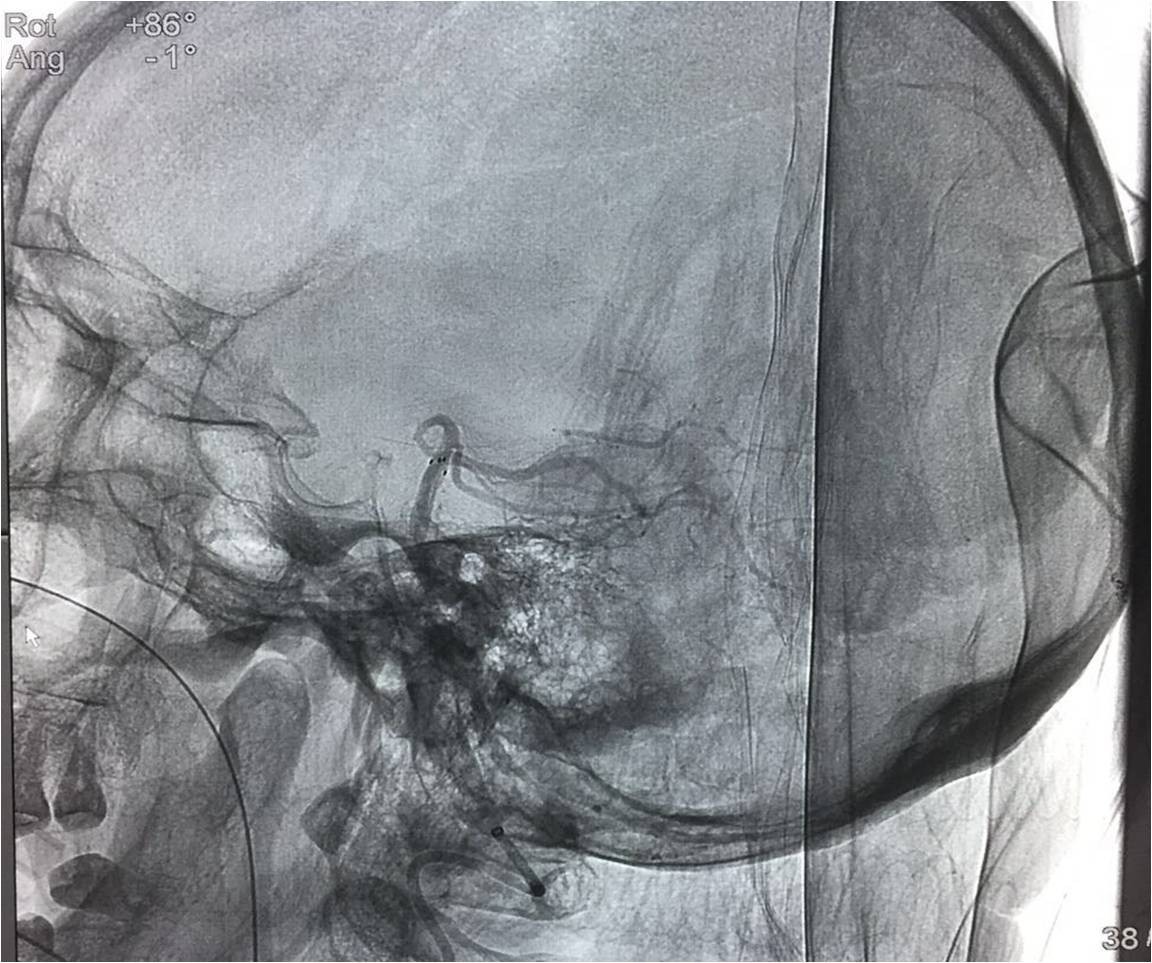

▼复查造影。

治疗效果、预后及随访情况:患者入院后严格按照《2015急性缺血性卒中血管内治疗中国指南》给予诊断治疗。患者术前NIHSS评分≥30分,术后第一天NIHSS评分19分,病情未进一步加重,肢体肌力恢复到3级,神志较前好转,病情稳定,进一步康复后,可恢复生活自理。